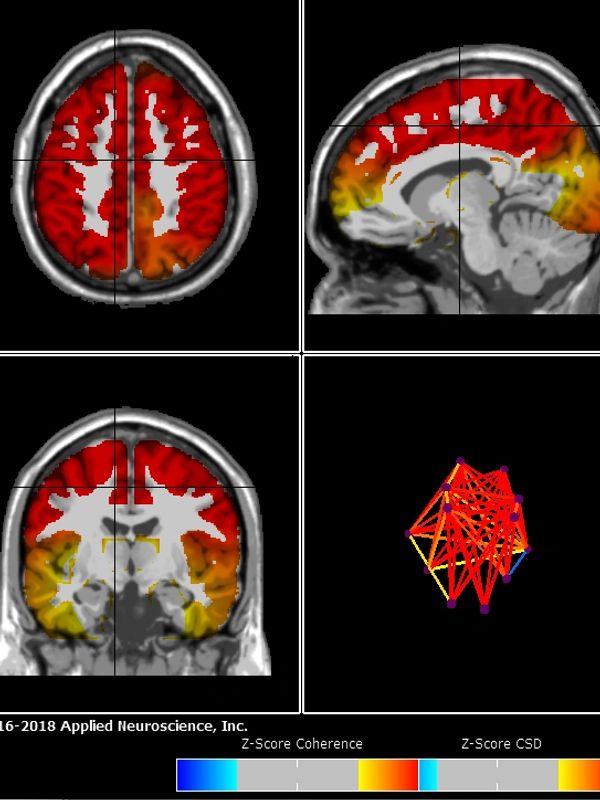

Also: We do not allow cell phones in the arena because of the frequencies. We need the arena 100% quiet during the session so the horse can hear the cues and counts, and the noise cancelling devices and the EEG works properly. Once the session starts, no one is allowed to walk in and out of the arena until the session ends and the rider has dismounted. Cell phones can be kept in your own personal vehicle, or we have a box that we keep them in during each session. We also ask that you do not wear fitbits, watches, or other devices that give off frequencies or record heart rates.